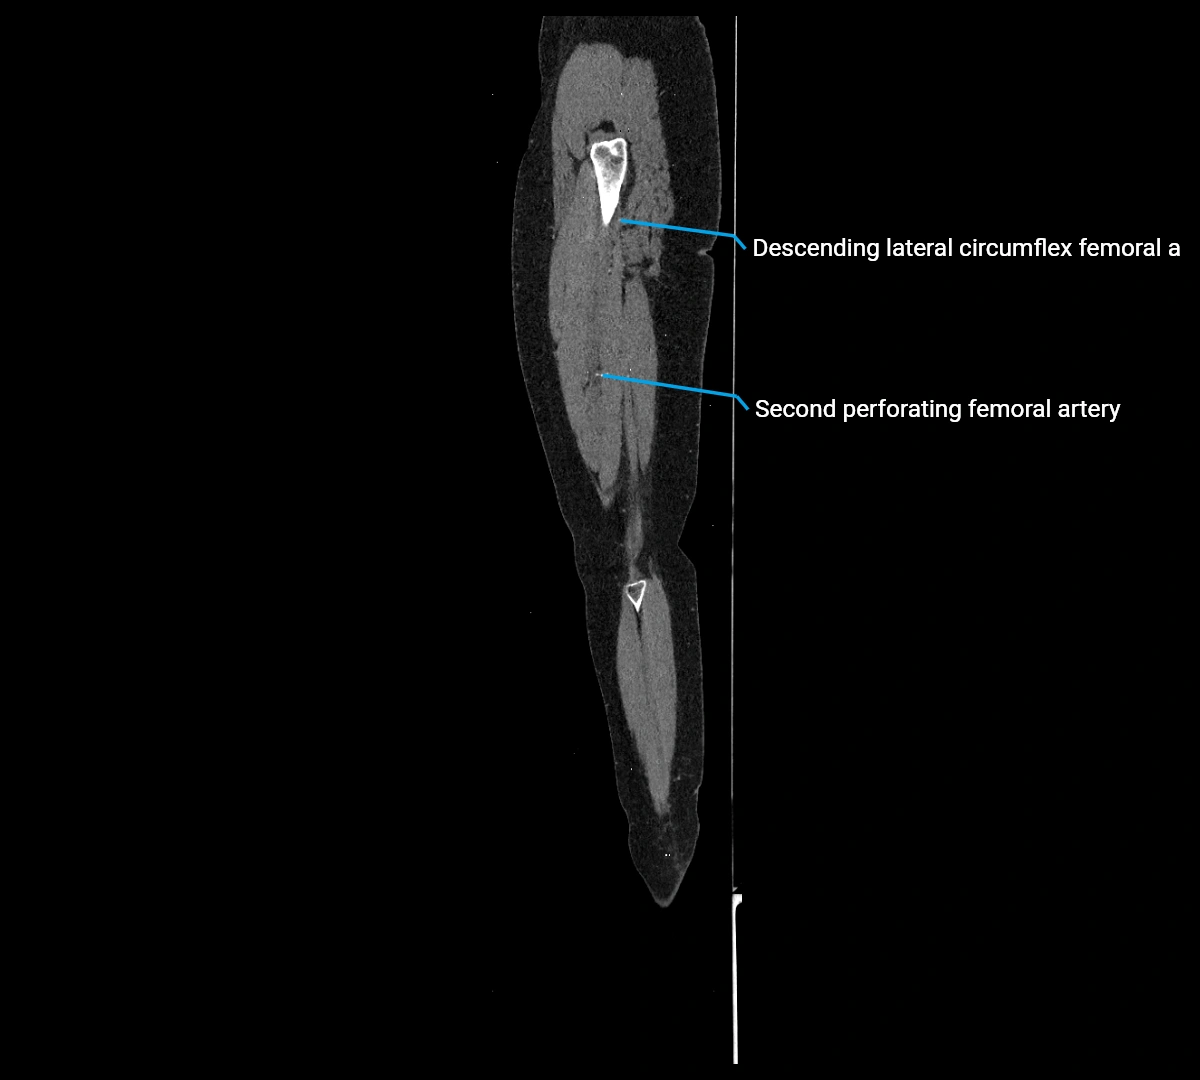

Contrast-enhanced CT (CTA):

• Gold standard for abdominal aortic imaging

• Provides excellent detail of lumen, wall, aneurysm, thrombus, and branch vessels

• Multiplanar and 3D reconstructions help in aneurysm measurement, stent graft planning, and dissection evaluation

• Detects acute rupture, traumatic injury, or occlusion with high sensitivity